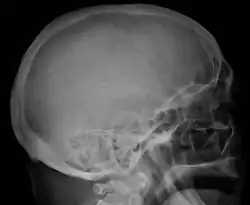

The diagnostic examination of a person with suspected multiple myeloma typically includes a skeletal survey. This is a series of X-rays of the skull, axial skeleton, and proximal long bones. Myeloma activity sometimes appears as "lytic lesions" (with local disappearance of normal bone due to resorption) or as "punched-out lesions" on the skull X-ray ("raindrop skull"). Lesions may also be sclerotic, which is seen as radiodense.[76] Overall, the radiodensity of myeloma is between −30 and 120 Hounsfield units (HU).[77] Magnetic resonance imaging is more sensitive than simple X-rays in the detection of lytic lesions. An MRI may supersede a skeletal survey, especially when vertebral disease is suspected. Occasionally, a CT scan is performed to measure the size of soft-tissue plasmacytomas. Nuclear Medicine Bone scans are typically not of any additional value in the workup of people with myeloma (no new bone formation; lytic lesions not well visualized on nuclear bone scan).

Skull X-ray showing multiple lucencies due to multiple myeloma -

Bone pain affects almost 70% of people with multiple myeloma and is one of the most common symptoms.[2]: 653 [23] Myeloma bone pain usually involves the spine and ribs and worsens with activity. Persistent, localized pain may indicate a pathological bone fracture. Involvement of the vertebrae may lead to spinal cord compression or kyphosis. Myeloma bone disease is due to the overexpression of receptor activator for nuclear factor κ B ligand (RANKL) by bone marrow stroma. RANKL activates osteoclasts, which resorb bone. The resultant bone lesions are lytic (cause breakdown) in nature. They are best seen in plain radiographs, which may show "punched-out" resorptive lesions (including the "raindrop" appearance of the skull on radiography). The breakdown of bone also leads to the release of calcium ions into the blood, leading to hypercalcemia and its associated symptoms.[24]